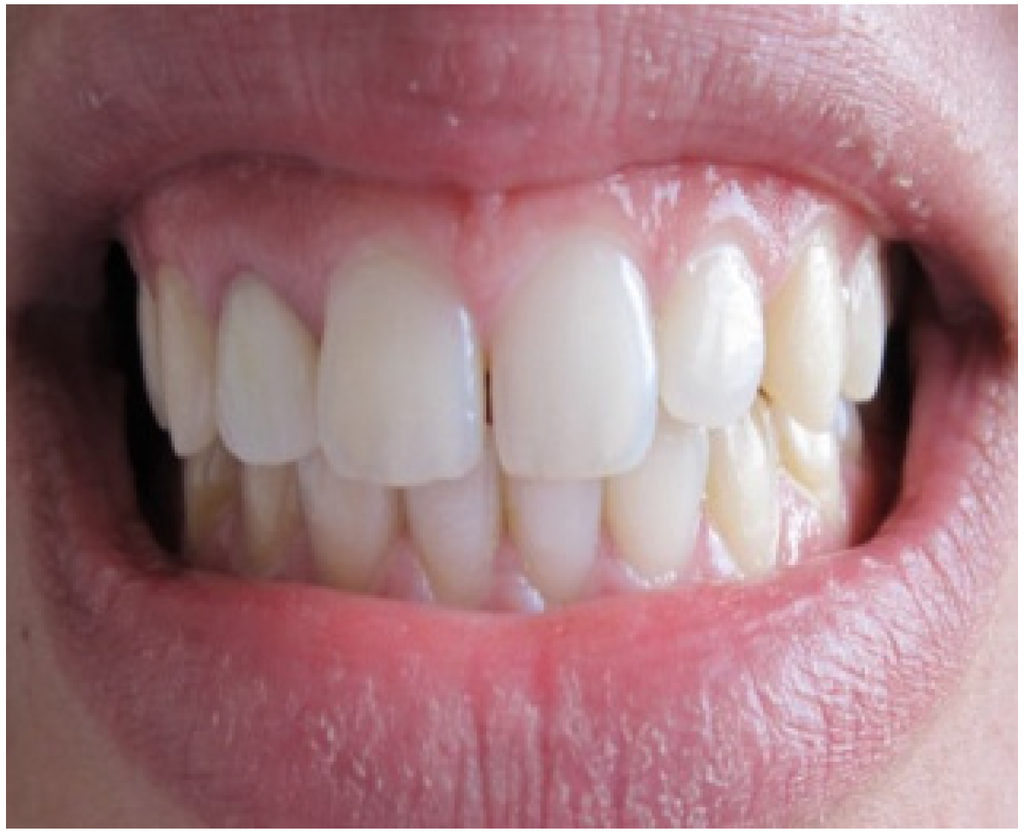

A 25-year-old dental student presented to the department of prosthetic dentistry with a chief complaint of poor aesthetics due to her imperfect metal ceramic single crown in the lateral incisor. She was bothered about the visible dark areas under the crown margins and requested an aesthetic rehabilitation. She also expressed her dissatisfaction with its color and shape. Intra oral examination showed dark gingival margins in the lateral incisor caused by metal frame (Figure 1). Soft tissues were evaluated as healthy with a wide band of attached gingiva in the maxillary region and a good oral hygiene.Visual assessment and Periodontal probing revealed a thick healthy gingival biotype with gingival thickness of 2 mm. and a sulcus depth of 2 mm. Bone sounding revealed a crest position in close relationship relative to anticipated post-surgical gingival margin level (2.5 mm). As the patient presents a thick periodontal biotype, this would significantly influence the post-operative procedure in favor of the esthetically desired outcome as this type is less prone to post-surgical recession.

Figure 1. Intra oral view showing the grayish shadow caused by the metal based crown.